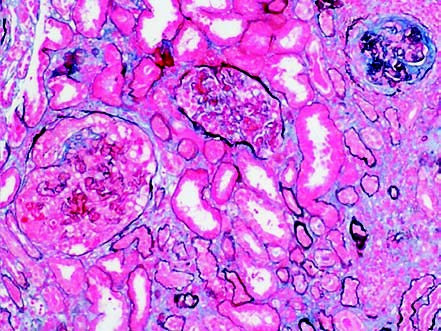

Immunofluorescence and electron microscopy typically reveal no immune complexes or electron-dense deposits, or only minimal deposition. Light microscopy often shows focal segmental necrosis of glomerular capillary loops and crescent formation, with lesions of varying stages.

Figure 1 Renal involvement in ANCA-associated small-vessel vasculitis, showing crescents of varying stages (PASM ×100)